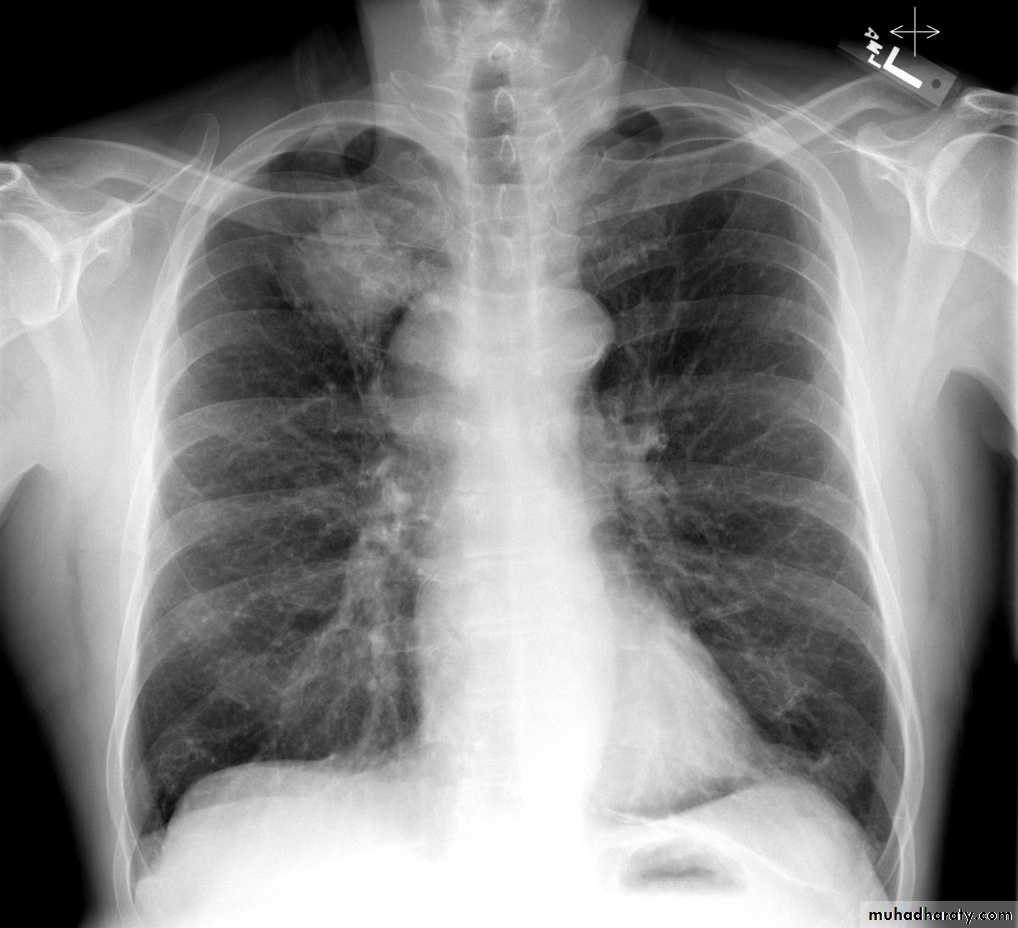

Bilateral hilar LAP

28.chest XR ( bilateral hilar lymph adenopathy )

29.chest XR ( bilateral hilar lymph adenopathy )